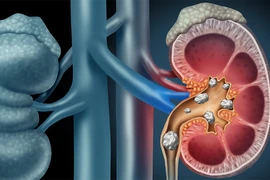

Ung thư thận là loại bệnh đứng thứ ba trong ung thư tiết niệu, chiếm 2,8% trong tổng số các bệnh ung thư, lại không có dấu hiệu và triệu chứng rõ ràng ở giai đoạn sớm. Vì thế người dân cần chú ý.

Ung thư thận là kết quả của một số tế bào thận phát triển không kiểm soát, dẫn đến một khối ác tính. Đây là một căn bệnh nguy hiểm, cần được điều trị càng sớm càng tốt.

Bệnh sỏi thận có diễn biến âm thầm, người mắc bệnh sỏi thận có thể không nhận ra cho tới khi đi khám. Nếu không được phát hiện và điều trị kịp thời thì rất có thể sẽ dẫn tới biến chứng suy thận.